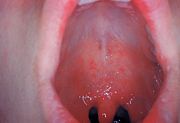

Rötung des Rachens (Enanthem)

Typisch für die Masern ist ein zweiphasiger Krankheitsverlauf: Auf die Inkubationszeit von 10 bis 14 Tagen folgt das drei bis vier Tage dauernde, uncharakteristische Prodromalstadium, auch Initialstadium genannt. Dieses äussert sich durch eine Entzündung der Schleimhäute des oberen (Katarrh mit Rhinitis), teilweise auch des mittleren Atemtraktes als trockene Bronchitis, sowie der Augenbindehäute (Konjunktivitis). Das Beschwerdebild in diesem Krankheitsstadium wird daher auch mit den Worten „verrotzt, verheult, verschwollen“ beschrieben. Dazu kann es zu Fieber bis 41 °C, Übelkeit, Halsschmerzen und Kopfschmerzen kommen. Die nur bei Masern vorkommenden Koplikflecken an der Wangenschleimhaut gegenüber den vorderen Backenzähnen (Prämolaren) sind eher selten zu beobachten und werden von manchen Autoren zu den atypischen Zeichen einer Maserninfektion gezählt.[25] Diese weissen, kalkspritzerartigen Flecken auf gerötetem Untergrund sind 1–2 mm gross und treten kurz vor dem Erscheinen des späteren Ausschlags auf.

Am 12. bis 13. Tag geht die Krankheit in das typische Exanthemstadium über, das oft mit einer typischen Schleimhautrötung (Enanthem) am weichen Gaumen beginnt. Am 14. bis 15. Tag breitet sich ein fleckig-knotiger (makulo-papulöser), zum Teil konfluierender, grossfleckiger Ausschlag (Exanthem) – typischerweise hinter den Ohren (retroaurikulär) beginnend – innerhalb von 24 Stunden über den ganzen Körper aus. Nach weiteren vier bis fünf Tagen bilden sich die Symptome in der Regel zurück. Als Überbleibsel des Exanthems kann eine kleieförmige Schuppung für kurze Zeit bestehen bleiben. Begleitend treten häufig Lymphknotenschwellungen (Lymphadenopathie) auf. Bei Erwachsenen verläuft die Krankheit oft schwerer als bei Kindern.